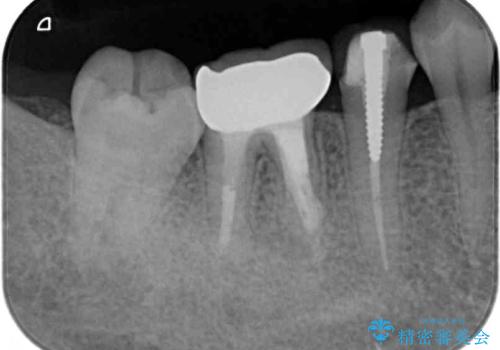

下顎大臼歯は歯冠部分が残っておらず、保存が難しいように思えましたが、まずは根管治療を行った上で補綴治療を行うこととしました。

奥歯は抜歯をせずに保存することができました。ただし、状態は決して良いとは言えないため、定期的に経過を見ていく必要があります。